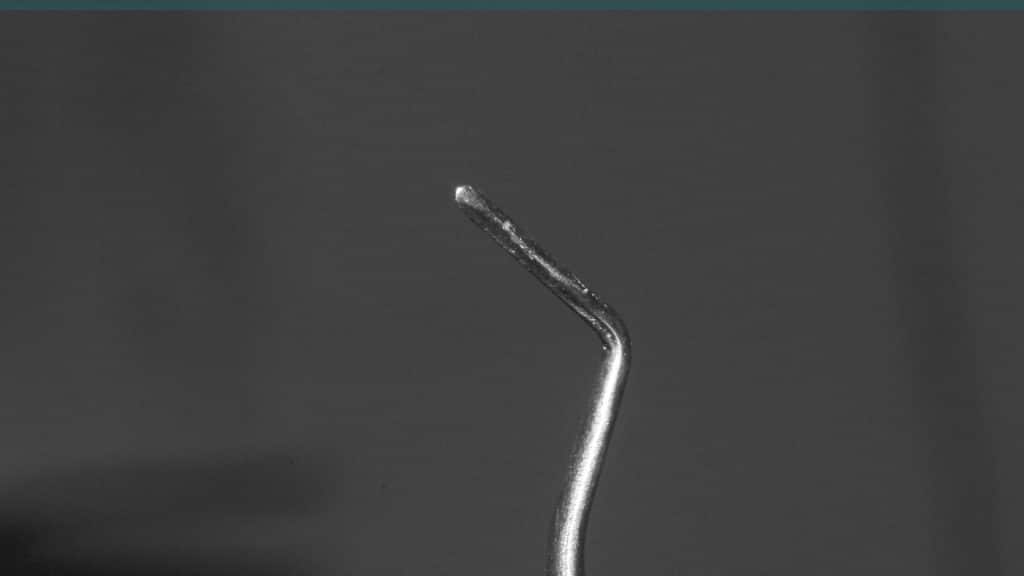

Immediate post-op